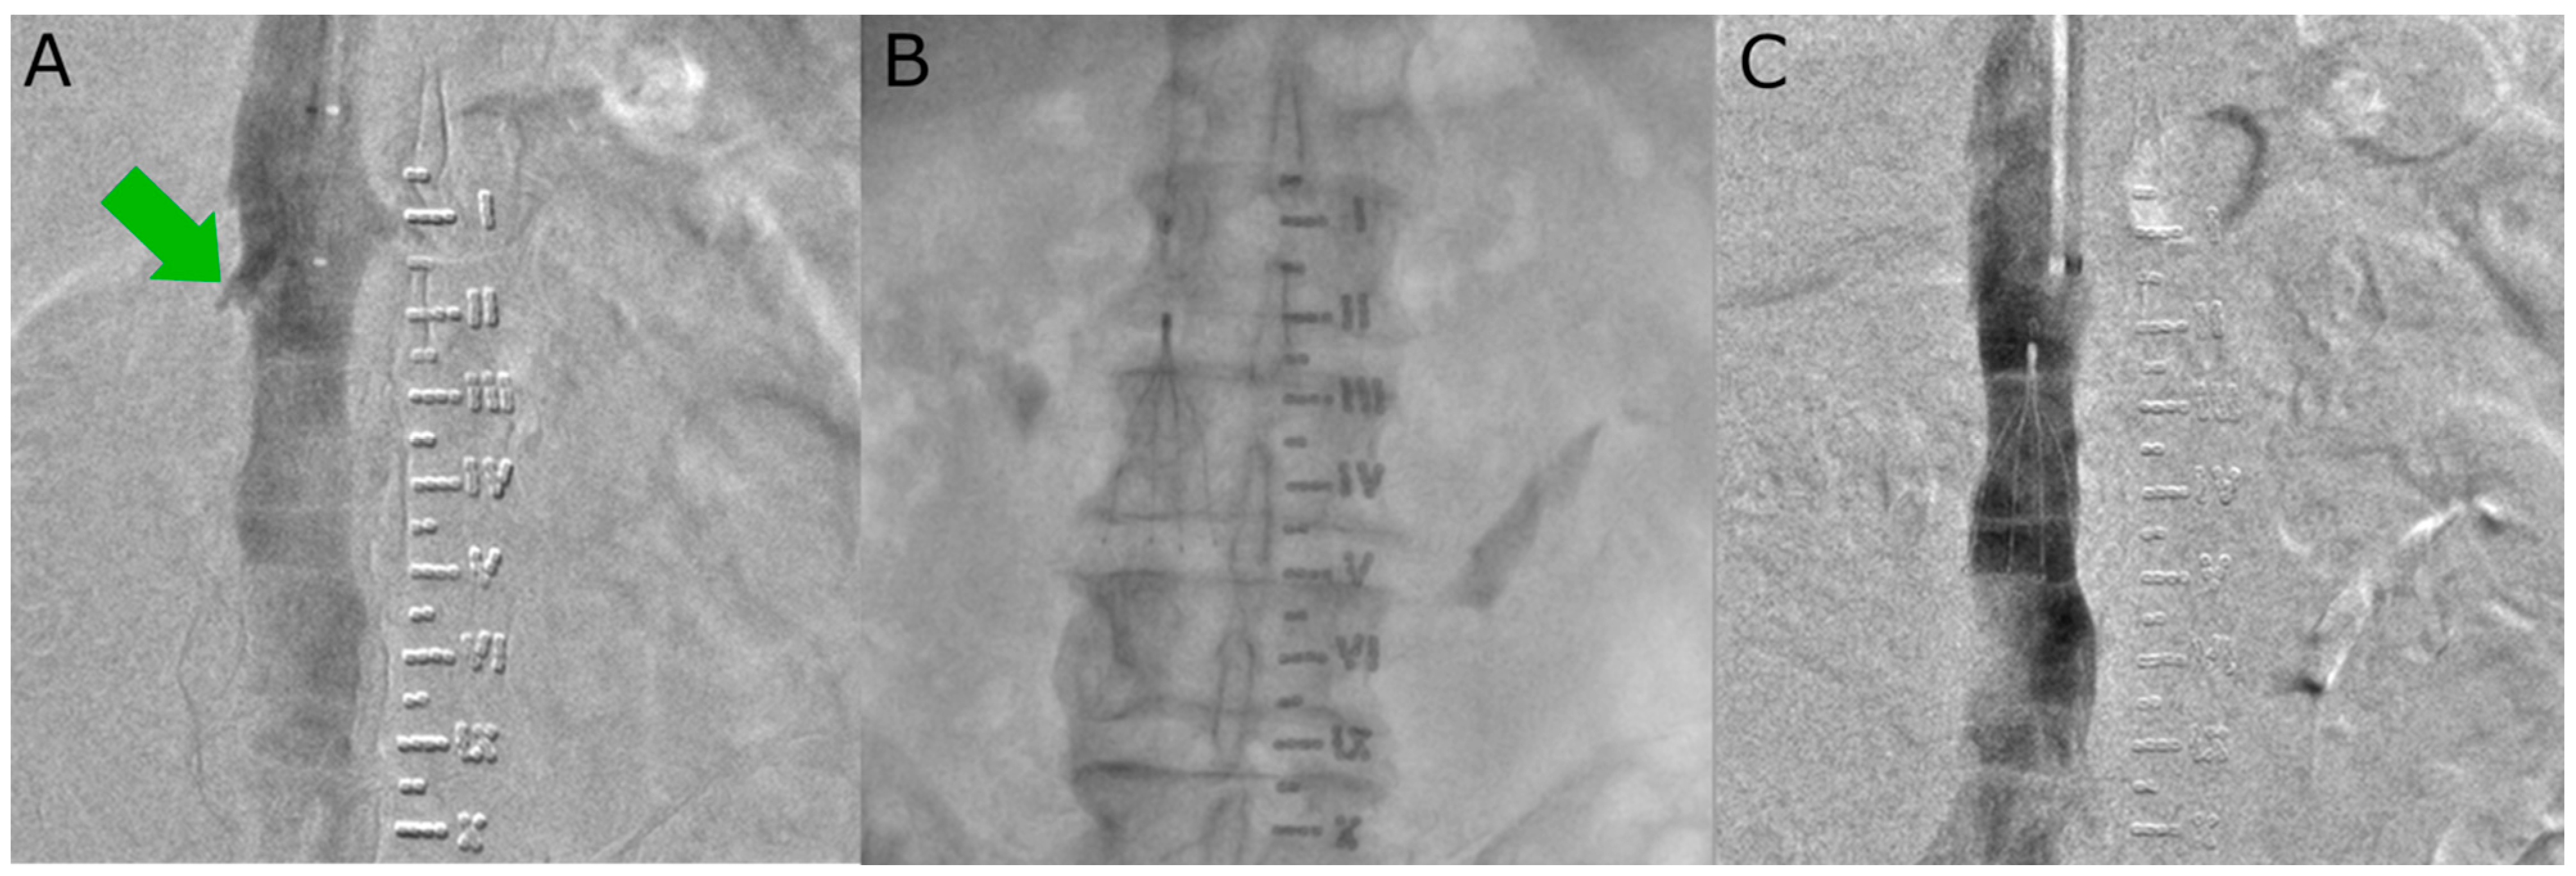

2.2. Procedural Details